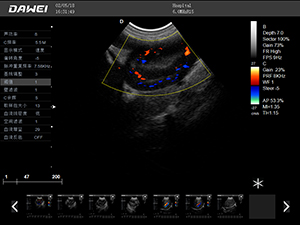

F5-VET彩色多普勒動物超聲診斷儀

F5-VET是一款性能可靠的獸用全數字彩色多普勒超聲診斷系統,基于Windows平臺 配置固態盤快速啟動 穩定可靠,融合了全面豐富的臨床應用,結合優異的人機工程學設計,推動了臨床診斷新趨勢。

·探頭接口:≥4個 可配備凸陣、微凸陣、線陣、相控陣、經直腸等各類獸用專用探頭,并配有犬、貓、馬等動物的專用測量軟件,是一款應用全面的獸用彩超。

·中小動物的肝、膽,脾、腎、膀胱、子宮、妊娠等各組織器官的檢查和病變的診斷